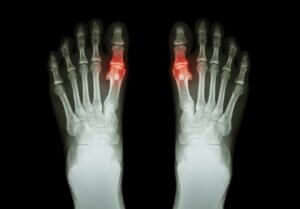

Fodsmerter har mange årsager, så lad os udforske nogle af dem her:

- Gigt